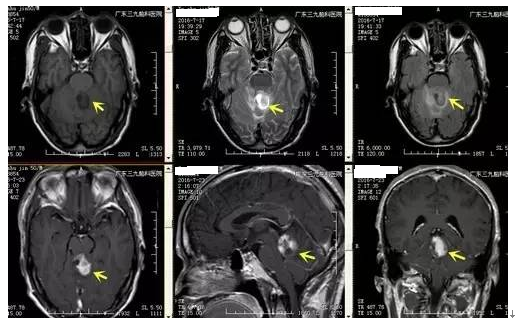

↑术前MR

间变型星形细胞瘤又称恶性星形细胞瘤,多形性星形细胞瘤,或Kernoban氏星形细胞瘤III级,是由星形细胞瘤恶变而来,其恶变发生率占14.25%。肿瘤在颅内大多数为浸润性生长,边界欠清晰,内密度不均匀,囊变多见,偶见钙化和出血,病变占位效应明显,周围可见血管源性水肿,早期扫描时病变可见不规则斑片强化,也少数为轻度强化或无强化。本例患者病变发生在小脑,CT见低密度影,内有斑片状稍高密度影,病灶中有一小囊性病变,囊变区呈低信号,稍高密度提示钙化可能,不规则强化。